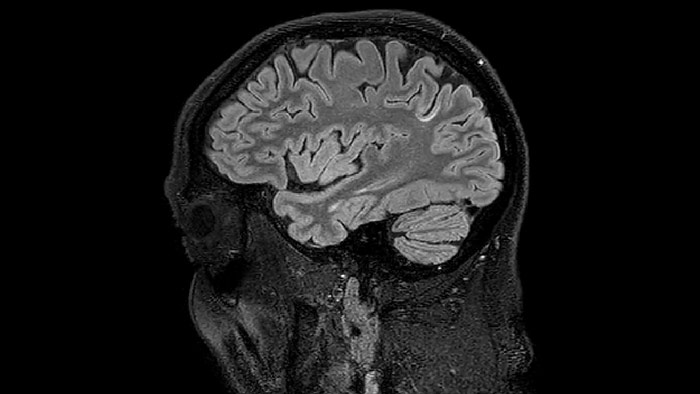

Accelerating scans helps researchers achieve their imaging goals

He says the accelerated scanning is achieved via the use of Compressed SENSE and MultiBand SENSE. “We can use Compressed SENSE acceleration factors of about 10 on a 3D FLAIR for instance, which is quite remarkable compared with what we saw with the Achieva. With 3D FLAIR, we can push the spatial resolution to 0.3 cubic mm and it works. Previously, our 3D FLAIR scans lasted about 8 minutes, but now with Elition they are five minutes. The SNR is also visibly better. Our SWI and QSM scans look fantastic. Also, since a lot of neuroimaging is EPI based, using the MultiBand SENSE technique can increase temporal resolution and make it possible to run complicated DTI scans relatively quickly.”

Sagittal 3D FLAIR with 0.3 mm3 voxel volume acquired in 5:12 min. using Compressed SENSE showing a (juxta)cortical MS lesion.